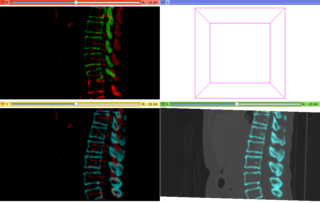

Bones near liver are segmented for two time point images of a liver. Time point A is red and B is green. The moving green image is registered on the red fixed image. The green image is transformed to the cyan image. The same transformation matrix on the cyan bone image is used to transformed the moving liver data set B.

| current | 23:50, 12 January 2012 | 985 × 625 (143 KB) | Ktdiedrich (talk | contribs) | Bones near liver are segmented for two time point images of a liver. Time point A is red and B is green. The moving green image is registered on the red fixed image. The green image is transformed to the cyan image. The same transformation matrix on the c |